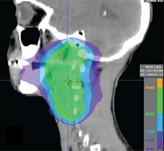

Stage IVA HPV-positive squamous cell carcinoma of the head and neck

They conducted a retrospective review of outcomes from 366 black and 236 white patients with nonmetastatic HNSCC who were treated with radiotherapy from 1990 to 2012. The results of the study were published in Cancer.